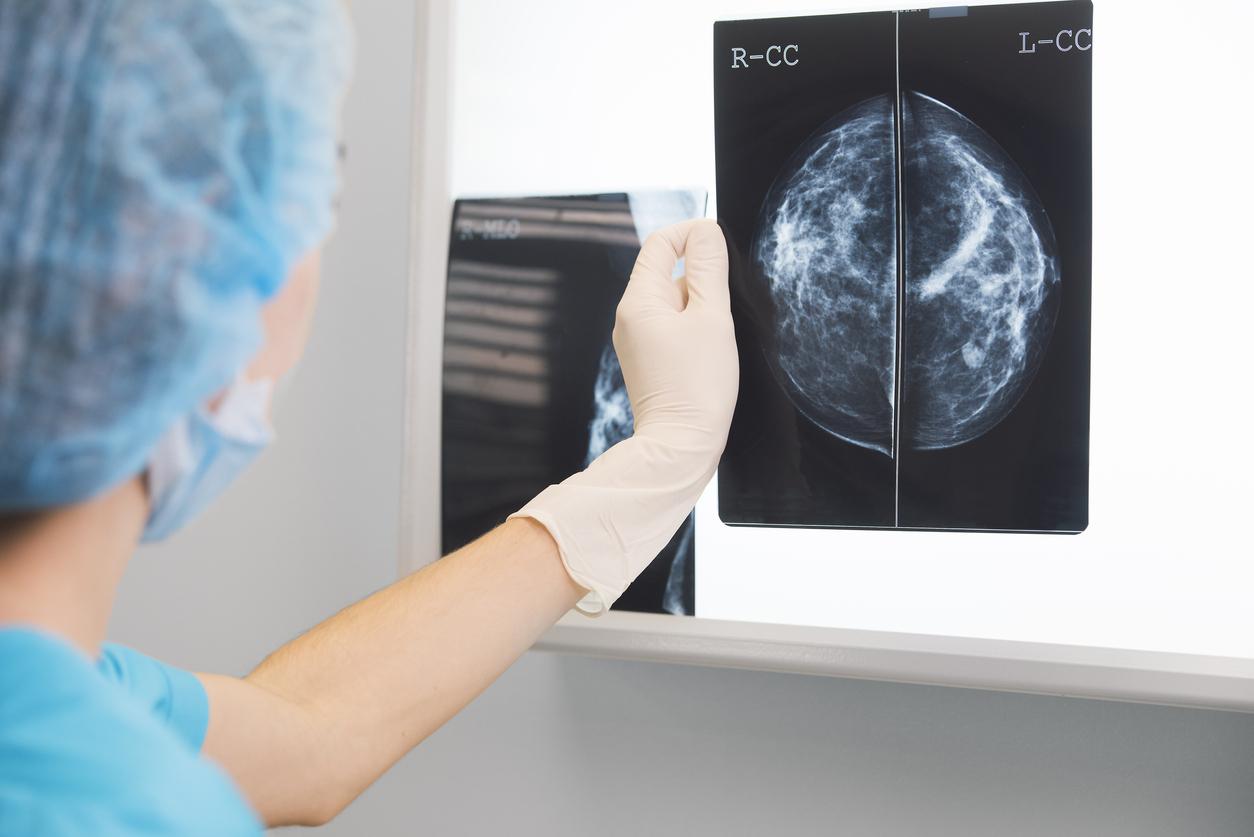

Le cancer du sein est l'un des cancers les plus répandus chez les femmes à travers le monde. Bien que de nombreux progrès aient été réalisés dans le diagnostic et le traitement de cette maladie, la formation de métastases reste l'un des principaux défis, réduisant drastiquement les taux de survie. Une équipe de chercheurs de l'Institut Curie, en collaboration avec d'autres institutions internationales, a identifié un processus biologique qui permet aux cellules cancéreuses du sein de migrer et de coloniser d'autres organes. Cette découverte, publiée dans la revue Nature Communications, met en lumière le rôle des exosomes dans la formation des métastases.